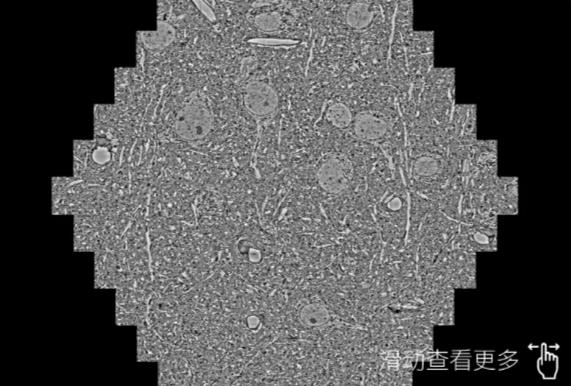

鼠脑切片。左图使用温州蔡司温州扫描电镜MultiSEM706对165μmx143pm面积区域成像,耗时仅需1.5秒。右图为鼠脑切片中30μm区域放大效果。样品由芝加哥大学B.Kasthuri提供。

使用蔡司高速温州扫描电镜MultiSEM对1mm²人脑皮层组织进行高分辨成像,并对其中的各种细胞结构进行三维重构分析。左图展示了2x3mm²组织平面中锥体神经元的三维重构效果。右图显示了局部体积神经元三维重构。图像由哈佛大学chtman实验室提供,渲染图由D. Berger 制作。